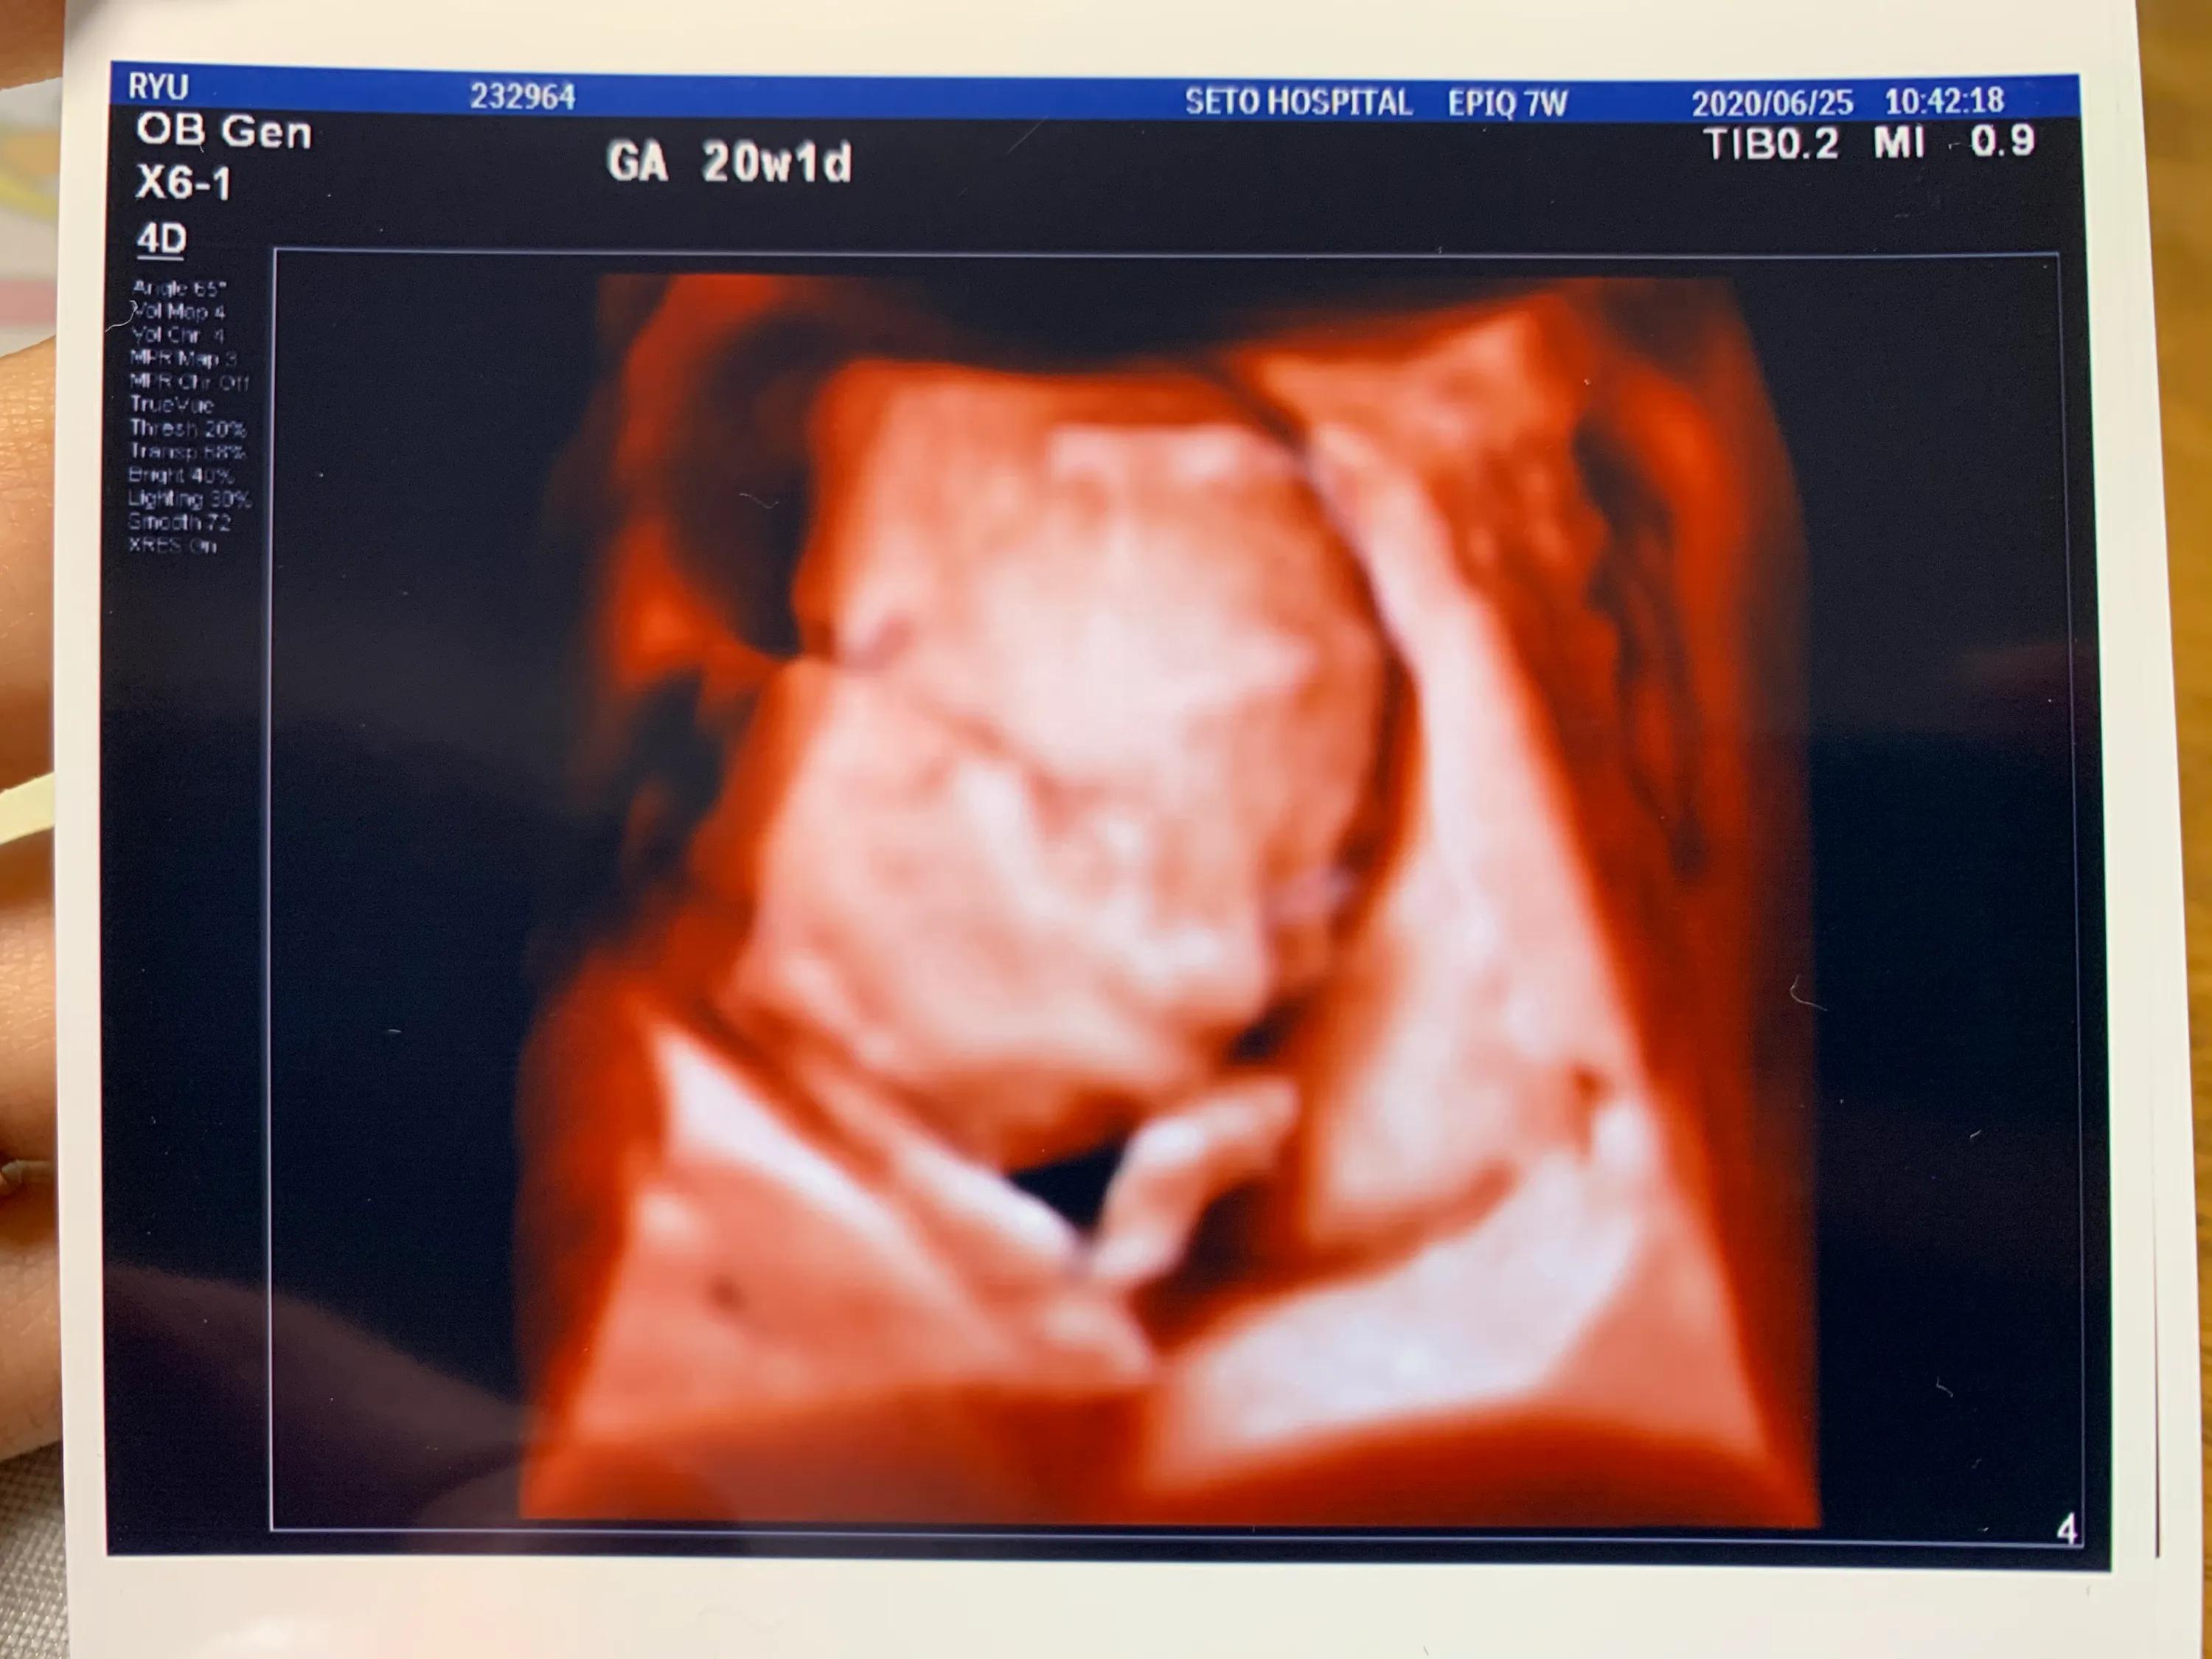

弟弟20周的B超照片

孕检项目也是最大的不同之一。国内感觉经常被抽血化验,而且早唐,唐筛,糖耐这些都是必做项目,有必要还要做无创或羊水穿刺。B超只有在重要的时间点才做,比如孕早期建卡时还有大排畸等。日本是很少抽血,印象中一共就抽了两三次,每次都会B超,根据B超数据来估算婴儿大小,羊水等,来判断胎儿和孕妇的健康。每次都会给宝宝可爱的B超照片进行留念。日本唐筛和糖耐这种不是必须做的,根据医生判断来进行检查,我就没做唐筛,但是医生让我做了糖耐。糖耐喝的是凉凉的汽水,比过国内的好喝。孕晚期胎心监护是差不多的,不过日本的次数没有国内多,国内几乎每次都做了。